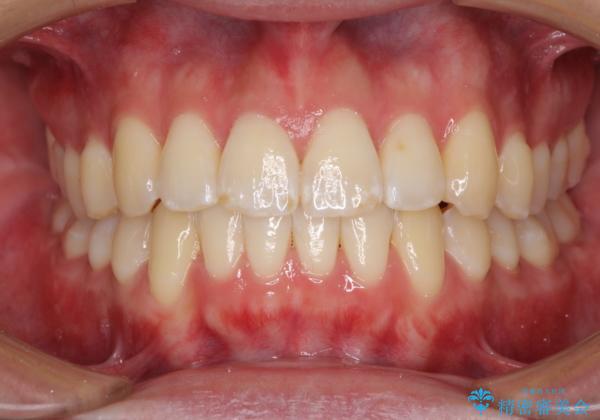

インビザラインで整った口元に

- 前歯のデコボコと若干口元が突出していることを気にして来院された患者様です。

全体的に軽微な叢生が認められ、口元もやや前方に突出していたため、インビザラインでのIPR(歯と歯の間を削る)と歯列全体の後方移動によって歯並びを整えることとしました。

上下ともに歯列の幅が狭かったため、側方に拡大することで前歯のデコボコや突出感を解消するためのスペースを獲得することができました。

歯並びが改善したことはもちろん、咬み合わせの改善まで実感することができ、患者様には大変満足していただけました。